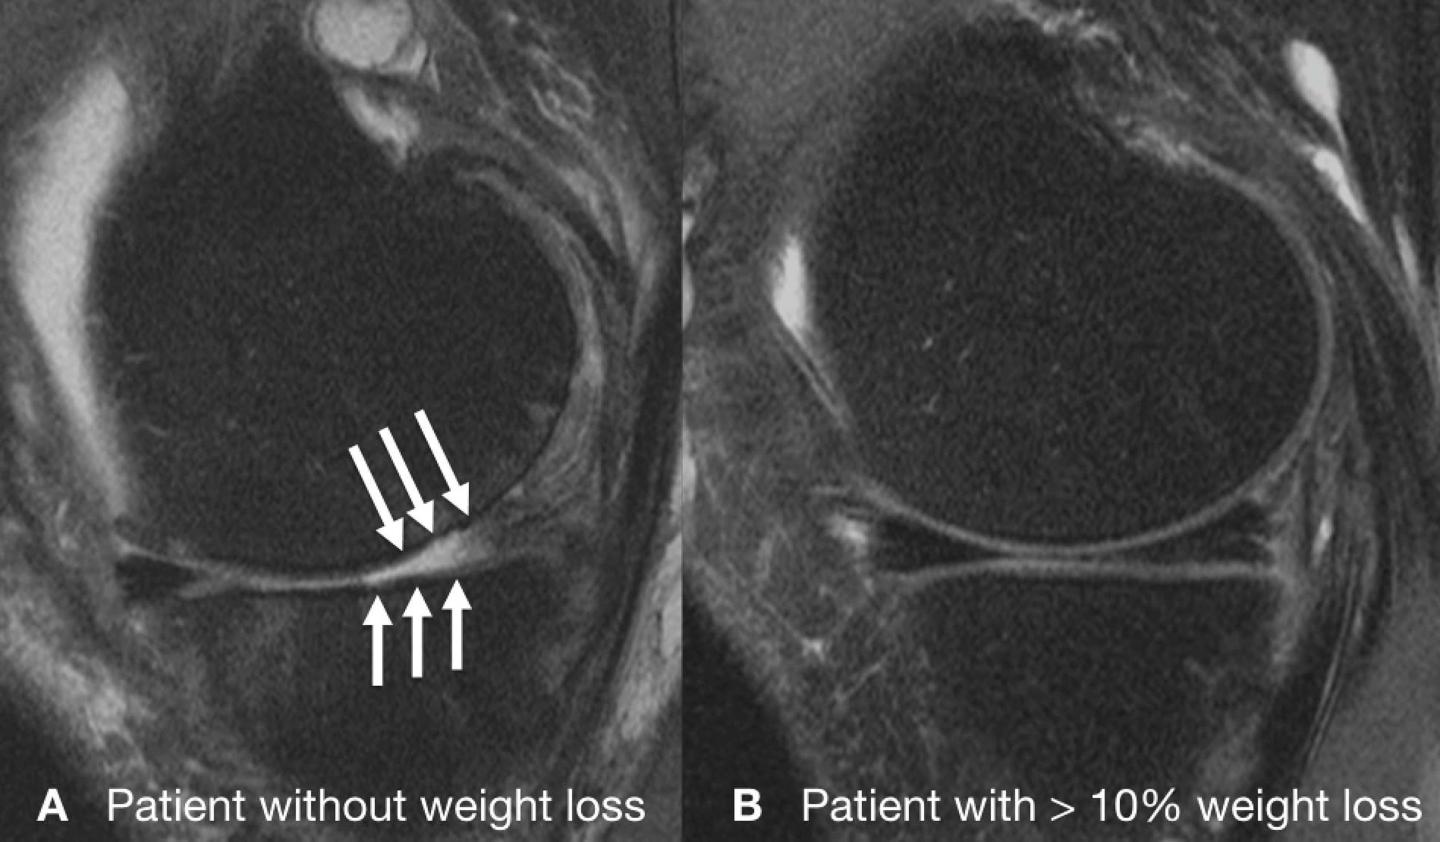

CHICAGO - Obese people who lose a substantial amount of weight can significantly slow down the degeneration of their knee cartilage, but only if they lose weight through diet and exercise or diet alone, according to a new MRI study presented today at the annual meeting of the Radiological Society of North America (RSNA).

Cartilage degeneration was significantly lower in the weight loss group, compared to the control group over the 96 months. However, this finding was only present among the patients who lost weight through diet and exercise or diet alone. Although patients who only exercised lost as much weight as patients who dieted alone or dieted and exercised, weight loss through exercise alone showed no significant difference in cartilage degeneration, compared to the group who lost no weight.

"These results add to the hypothesis that solely exercise as a regimen in order to lose weight in overweight and obese adults may not be as beneficial to the knee joint as weight loss regimens involving diet," Dr. Gersing said.